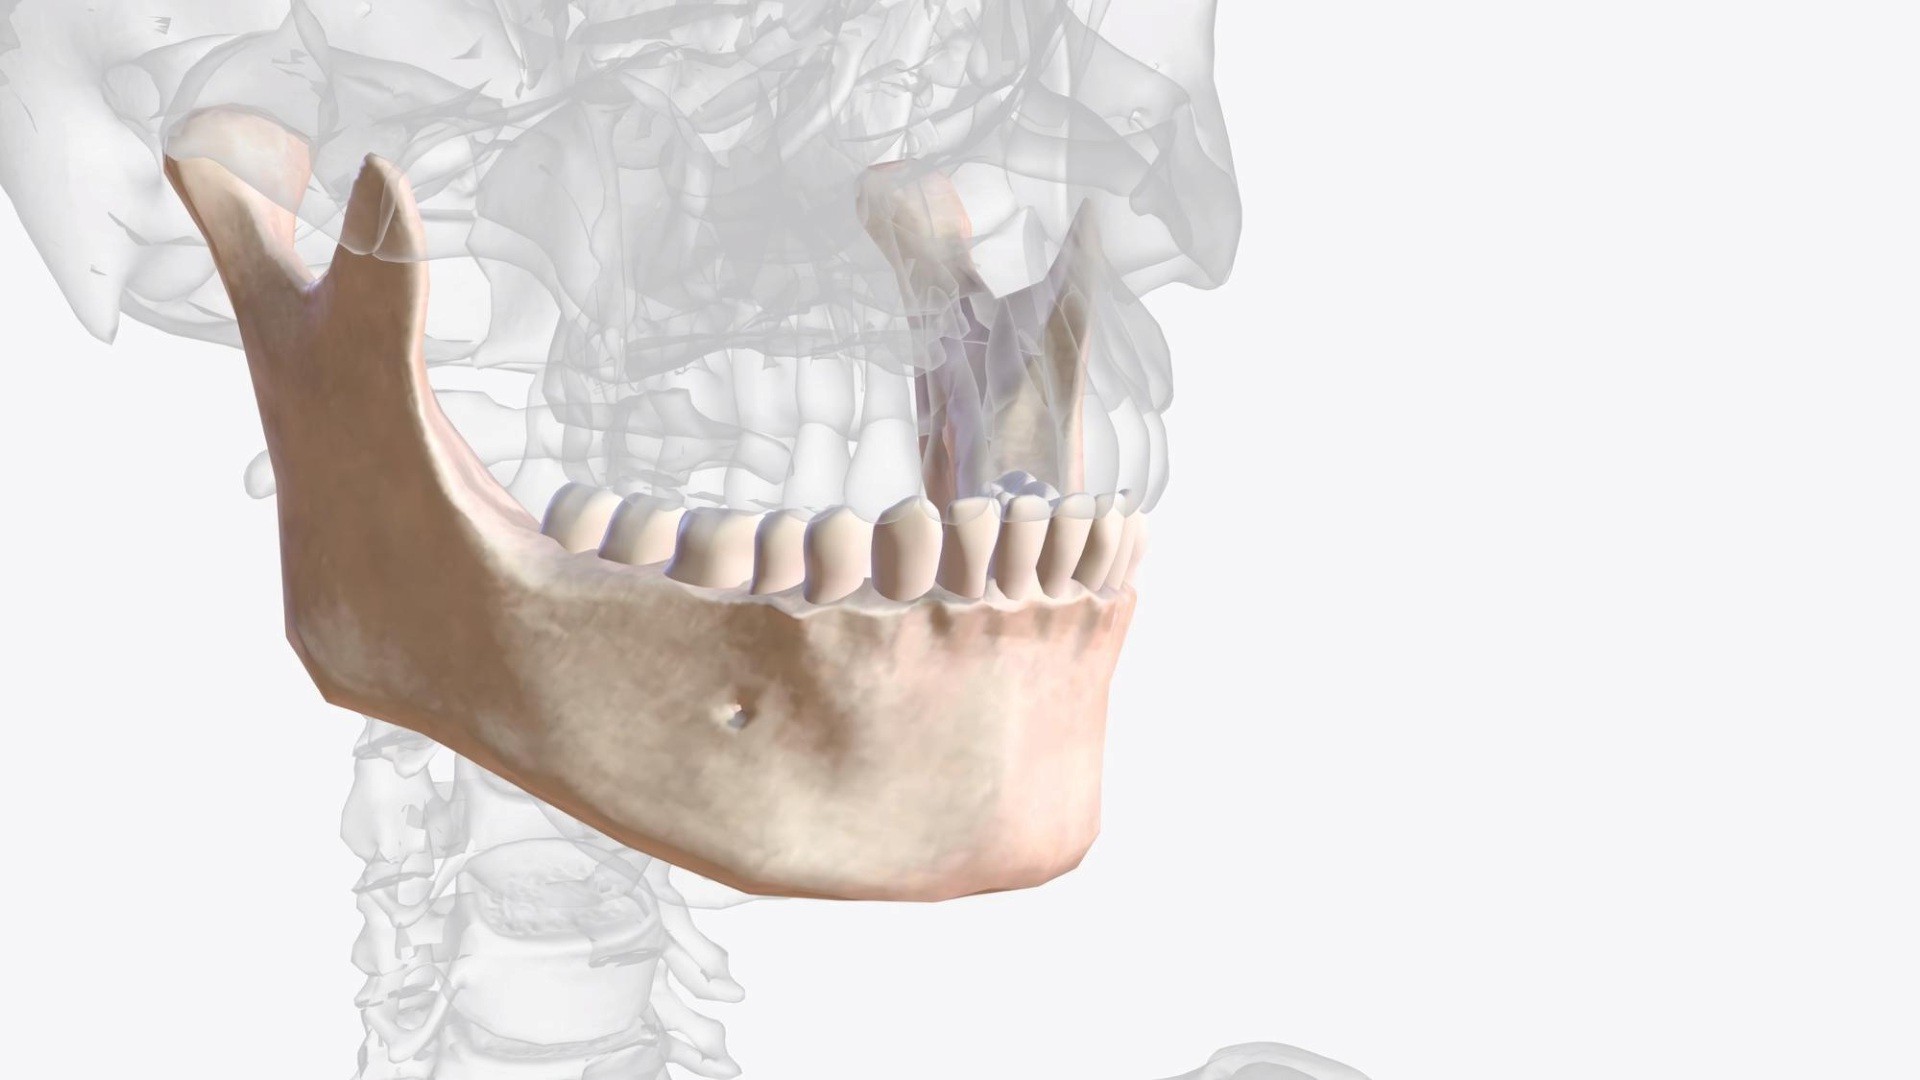

Upper Jawbone

Growth stop at ~8years old

Lower Jawbone

Peak growth (girl): ~12 years old

Peak growth (boy): ~14 years old

• Underdeveloped upper jaw trapping and stopping the lower jaw from growing

• Airway becoming more and more restricted

When the upper jaw doesn’t develop fully, the nasal airway becomes restricted. The result? The body compensates by altering facial growth, and your child may adjust how they breathe and even their neck posture.